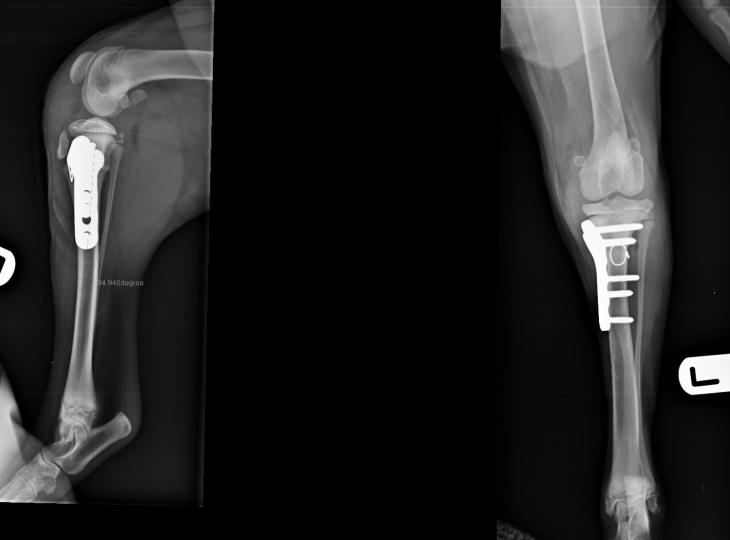

Figure 1. Tibial plateau levelling osteotomy using a broad locking plate and screws in a 45kg Labrador